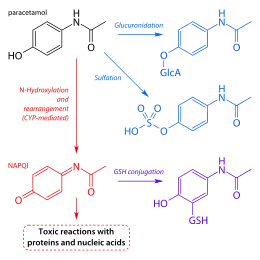

Paracetamol poisoning can occur accidentally or as an attempt to die by suicide. Risk factors for toxicity include alcoholism, malnutrition, and the taking of certain other hepatotoxic medications.[1] Liver damage results not from paracetamol itself, but from one of its metabolites, N-acetyl-p-benzoquinone imine (NAPQI).[6] NAPQI decreases the liver's glutathione and directly damages cells in the liver.[7] Diagnosis is based on the blood level of paracetamol at specific times after the medication was taken.[1] These values are often plotted on the Rumack-Matthew nomogram to determine level of concern.[1]

When taken in normal therapeutic doses, paracetamol has been shown to be safe.[14] Following a therapeutic dose, it is mostly converted to nontoxic metabolites via Phase II metabolism by conjugation with sulfate and glucuronide, with a small portion being oxidized via the cytochrome P450 enzyme system.[35] Cytochromes P450 2E1 and 3A4 convert approximately 5% of paracetamol to a highly reactive intermediary metabolite, N-acetyl-p-benzoquinone imine (NAPQI).[35][14][36][37][38] Under normal conditions, NAPQI is detoxified by conjugation with glutathione to form cysteine and mercapturic acid conjugates.[35][39]

In cases of paracetamol overdose, the sulfate and glucuronide pathways become saturated, and more paracetamol is shunted to the cytochrome P450 system to produce NAPQI. As a result, hepatocellular supplies of glutathione become depleted, as the demand for glutathione is higher than its regeneration.[39] NAPQI therefore remains in its toxic form in the liver and reacts with cellular membrane molecules, resulting in widespread hepatocyte damage and death, leading to acute liver necrosis.[35][40] In animal studies, the liver's stores of glutathione must be depleted to less than 70% of normal levels before liver toxicity occurs.[36]

Acetylcysteine

Acetylcysteine, also called N-acetylcysteine or NAC, works to reduce paracetamol toxicity by replenishing body stores of the antioxidant glutathione. Glutathione reacts with the toxic NAPQI metabolite so that it does not damage cells and can be safely excreted.[67] NAC was usually given following a treatment nomogram (one for patients with risk factors, and one for those without) but the use of the nomogram is no longer recommended as the evidence base to support the use of risk factors was poor and inconsistent and many of the risk factors are imprecise and difficult to determine with sufficient certainty in clinical practice.[68] Cysteamine and methionine have also been used to prevent hepatotoxicity,[69] although studies show that both are associated with more adverse effects than acetylcysteine.[20] Additionally, acetylcysteine has been shown to be a more effective antidote, particularly in patients presenting greater than 8 hours post-ingestion[70] and for those who present with liver failure symptoms.[61]